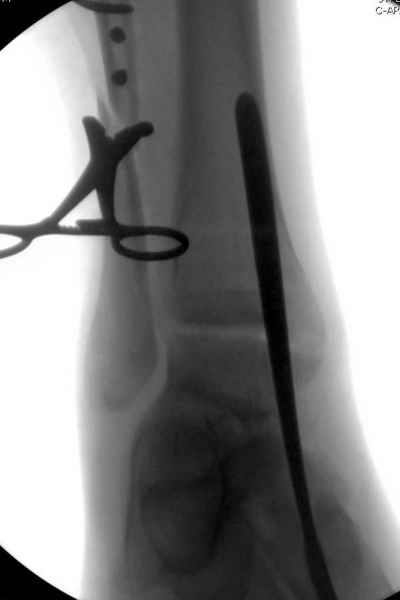

Мы бы, сблизив берцовые кости чрескожно наложенным репозиционным зажимом, провели позиционный межберцовый винт чуть ниже пластинки в положениий максимального тального сгибания стопы и ... на следующий день разрешили бы полностью наступать без гипса, брейса и т.п., но в обуви с небольшим каблуком 2-3 см и супинатором. Через месяц-полтора -винт удалить (если конечно не сломается).

Перелом типа Вебер С с эверсионным механизмом травмы всегда сопровождается повреждением дистального межберцового синдезмоза, поэтому вместе с фиксацией переломов лодыжек( малоберцовой кости) автоматом выполняется фиксация синдесмоза винтом, который обычно удаляется через 8 недель -

перед началом полной нагрузки на ногу.

Спустя 4 недели закрытая ( без отрытия зоны синдесмоза) репозиция может оказаться проблематичной, но все равно стоит попробовать из 1см разреза ввести тягловый винт и нтраоперационно проконтролировать межберц. синдесмоз. Предварительно стоит обсудить с больным вероятность открытия синдесмоза при безуспешности закрытой репозиции.

С мнением «провести позиционный межберцовый винт чуть ниже пластинки в положениий тыльного сгибания стопы» согласен, но я бы нагрузку начал через три недели и удаление шурупа можно провести через 6-8 недель.

Для облегчения удаления сломанных шурупов (случается часто) рекомендую фиксацию двумя 3.5мм кортикальными шурупами на 3 мм длиннее, тот же сломанный шуруп легко удаляется с медиальной стороны.

Здесь похожий случай трехнедельной давности, перелом почти сросся и была укорочена малоберцовая, на операции длину малоберцовой смогли восстановить только после того, когда проксимальнее пластины ввели шуруп и использовали его как толкатель, с помощбю дистракционого инструмента (lamina spreader).

Меньше всего волнует положение медиальной лодыжки - в любое время можно провести остео или реостеосинтез, при несращении можно просто резецировать без ущерба для движений в голеностопе. Здесь обошлись фиксацией одним 4 мм канюлированным шурупом.